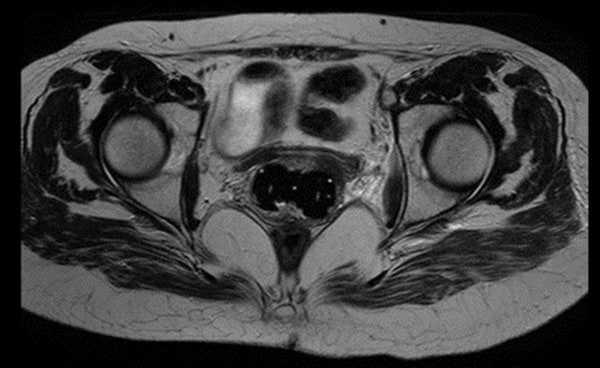

医科达为妇科近距离治疗提供了多种施源器,适用于从腔内到组织间插植等各种应用,可在妇科近距离治疗中提升更加精确的剂量杀死癌细胞。

could not find asset妇科施源器主要包括